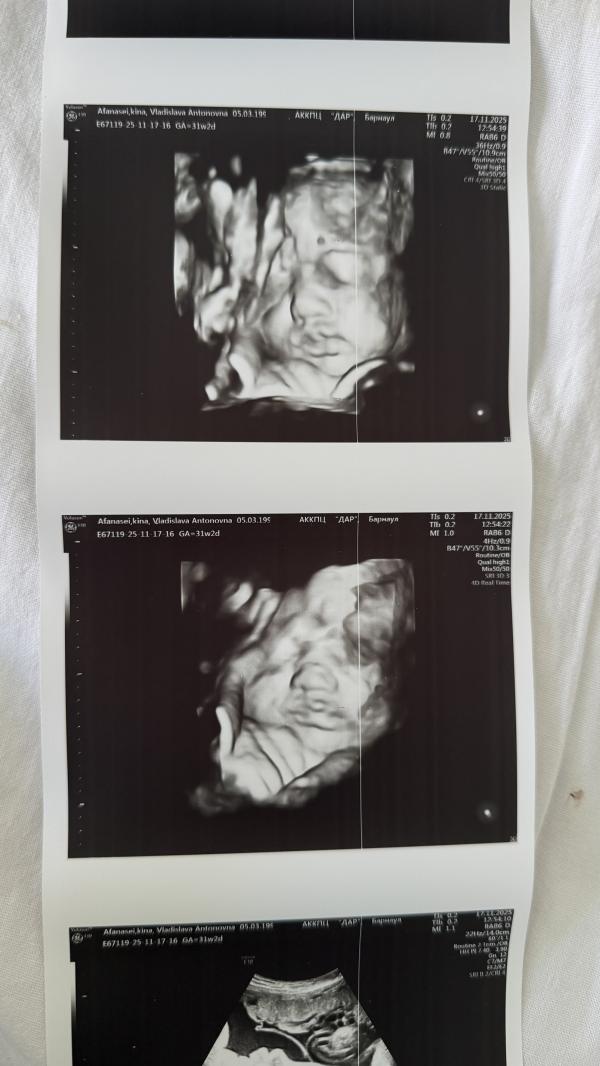

Поставили пессарий, посмотрели по узи - все хорошо. Единственное, на скрининг надо будет отдельно талон брать, так как в стационаре его не могут сделать. Но узистка все равно смогла сфотографировать одну из девчонок 😍

Красавицы ☺️